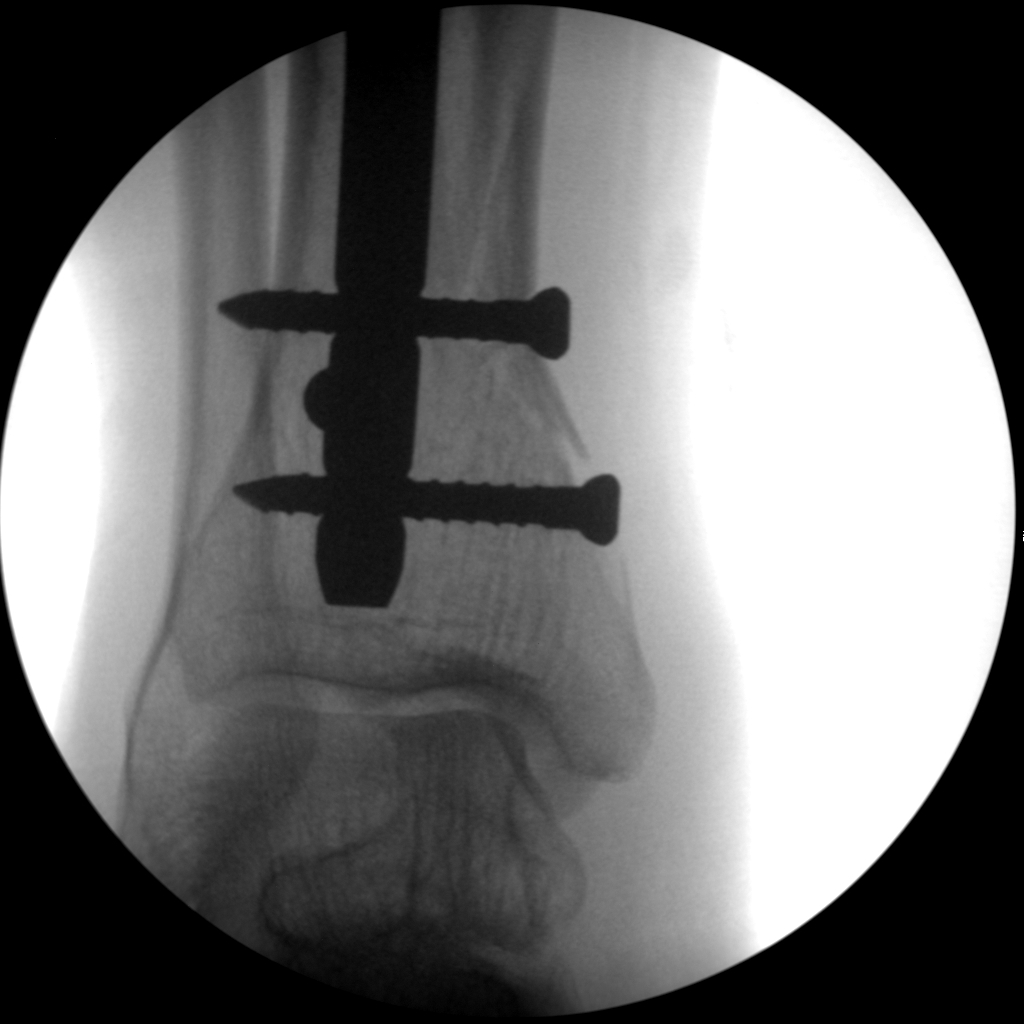

Hip fixation

Long bone nailing